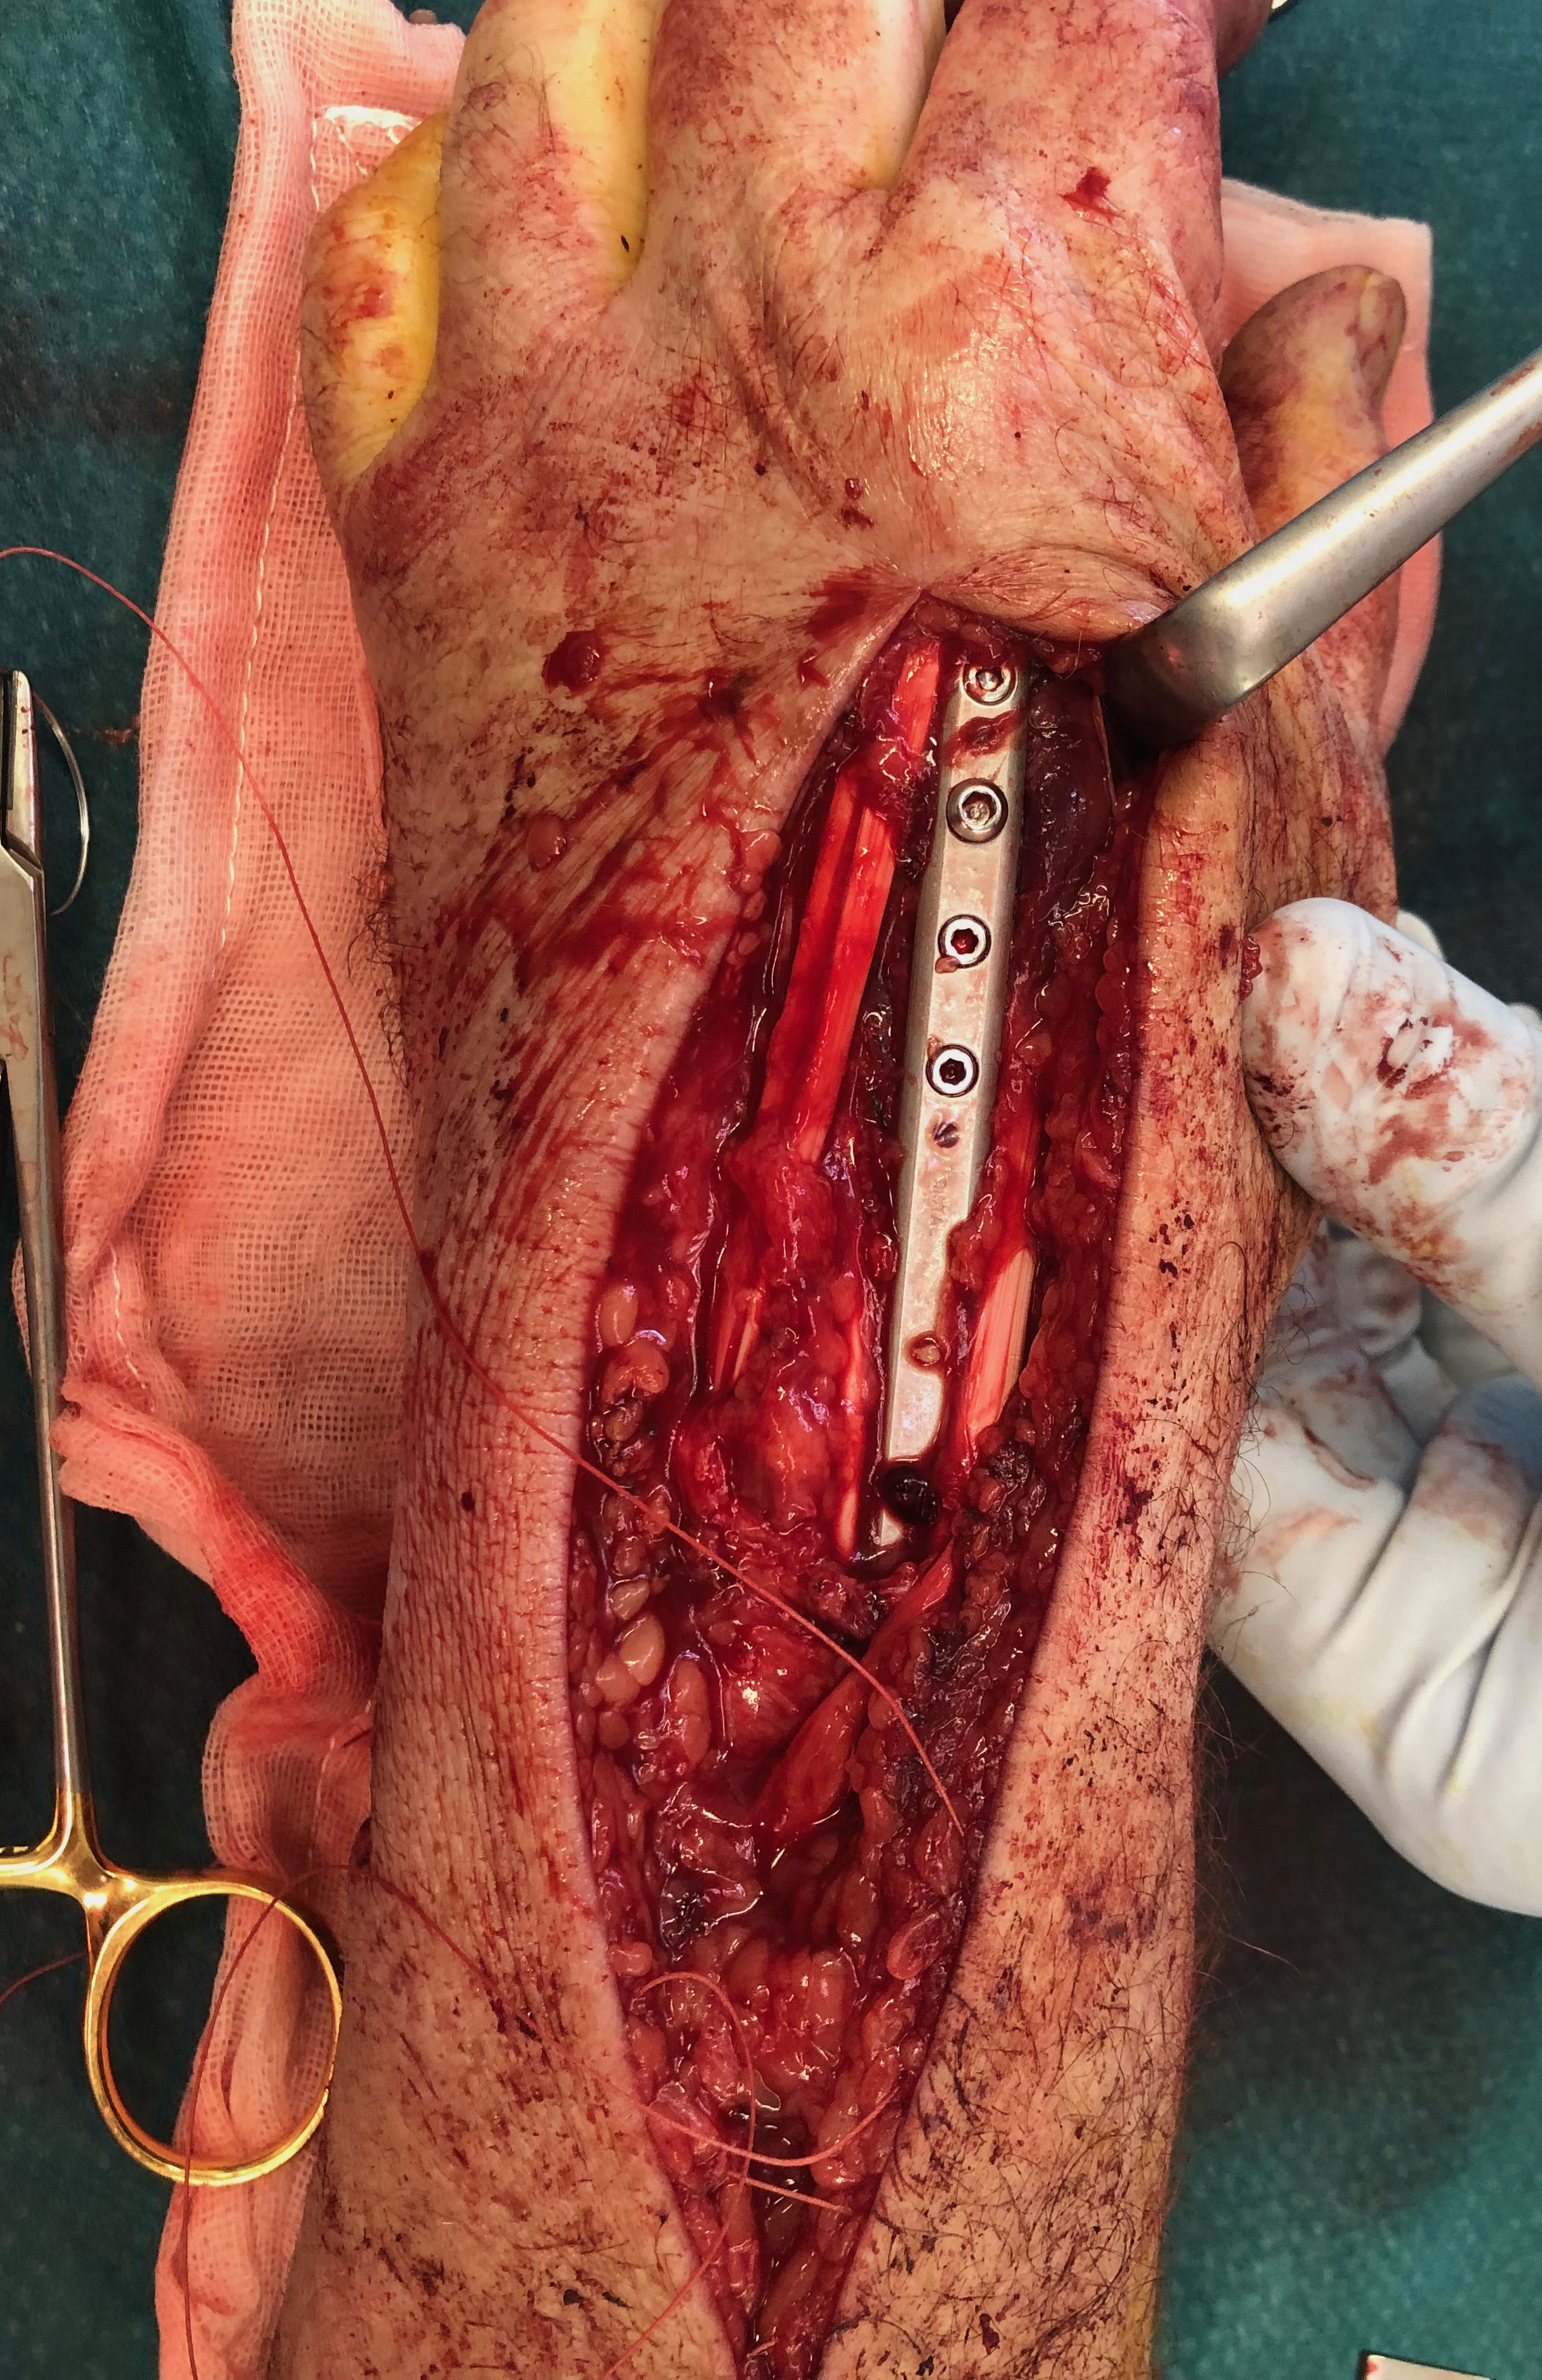

Volar locking plate technique

AO surgery modified Henry to distal forearm

Vumedi volar locking plate distal radius

Bed of FCR approach

- incision over FCR and mobilize ulnarly

- divide fascia in bed of FCR and retract radial artery laterally

- L shaped released of pronator quadratus

- cannot make volar capsulotomy - divides radiocarpal ligaments and causes instability

- elevate 1st extensor compartment (APL / EPB)

- release brachioradialis from radial styloid

Reduce fragments and temporarily stabilize with K wires

- apply volar plate with screw fixation in scaphoid and lunate fragments

- ensure not beyond watershed line to avoid flexor tendon irritation / rupture

- engage dorsal cortex but not too long to prevent EPL rupture

- on lateral, raise hand 30o to view joint

- +/- radial styloid plate if required